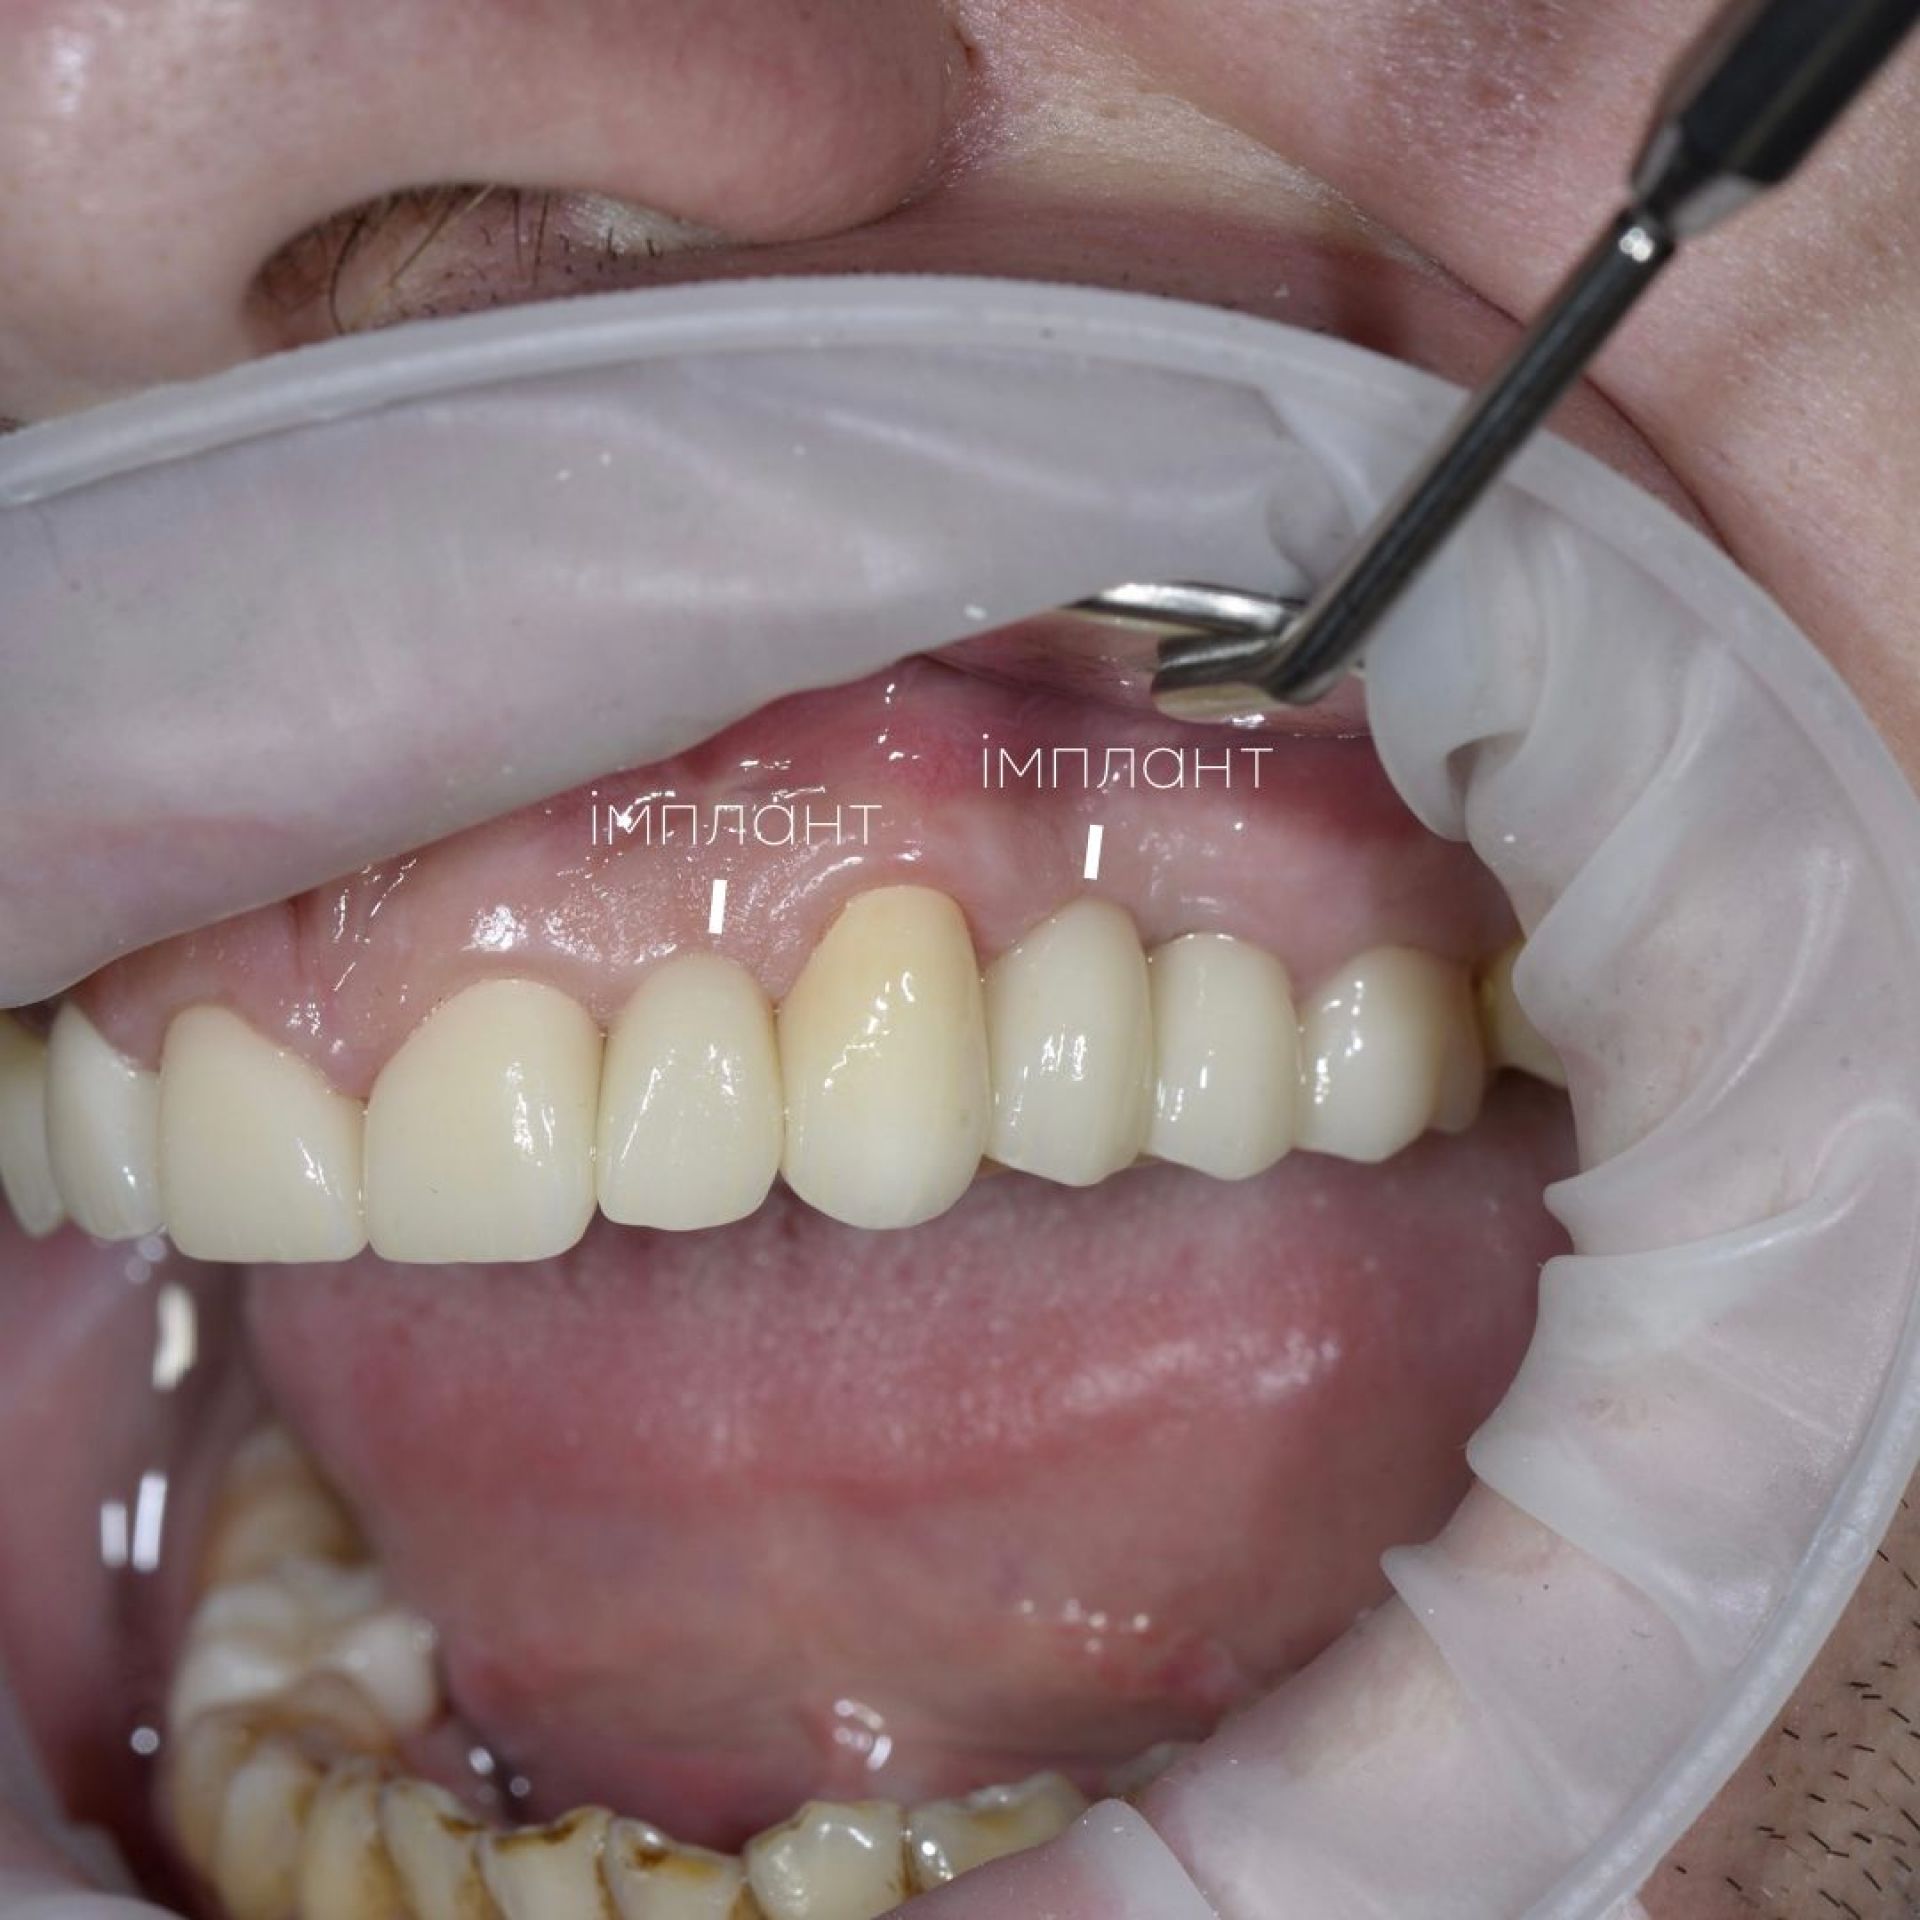

Імплант – це штучний корінь зуба, який виготовляється з титану. Він хірургічно вставляється в щелепну кістку, на ньому фіксується коронка, міст або протез. Імпланти відновлюють не лише естетику посмішки, але й функціональність зубів, даруючи Вам комфорт та впевненість.

Як відбувається сам процес імплантації в AsProDent:

- в місце відсутнього кореня вживлюється титановий імплант

- після приживлення імпланту, а це від 2-х до 6-ти місяців встановлюється формувач ясен

- пізніше встановлюється абатмент та тимчасова коронка

- завершальним етапом буде встановлення постійної коронки